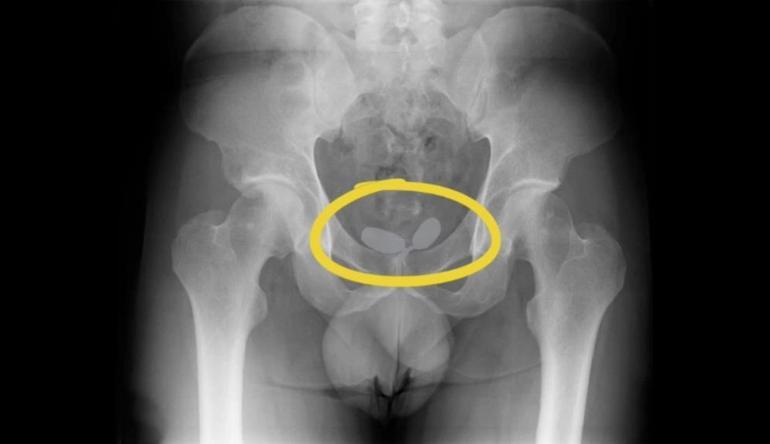

Alınan istihbarat doğrultusunda 2’si yabancı uyruklu toplamda 5 kişi yakalanarak gözaltına alındı. Yapılan röntgen muayenesinde, uyuşturucu kaçakçılarının akılalmaz oyunu ortaya çıktı.

Yapılan röntgen muayenesinde, Alman uyruklu kadının cinsel organında prezervatifler içerisine gizlenmiş uyuşturucular ele geçirildi. Diğer Alman yabancı uyruklu erkeğin ise uyuşturucuları anüsüne gizlediği belirlendi. Yapılan muayene sonrası; 21,19 gram eroin, 12,70 gram kokain, 7,76 gram amfetamin, 7 adet sentetik ecza ele geçirildi.